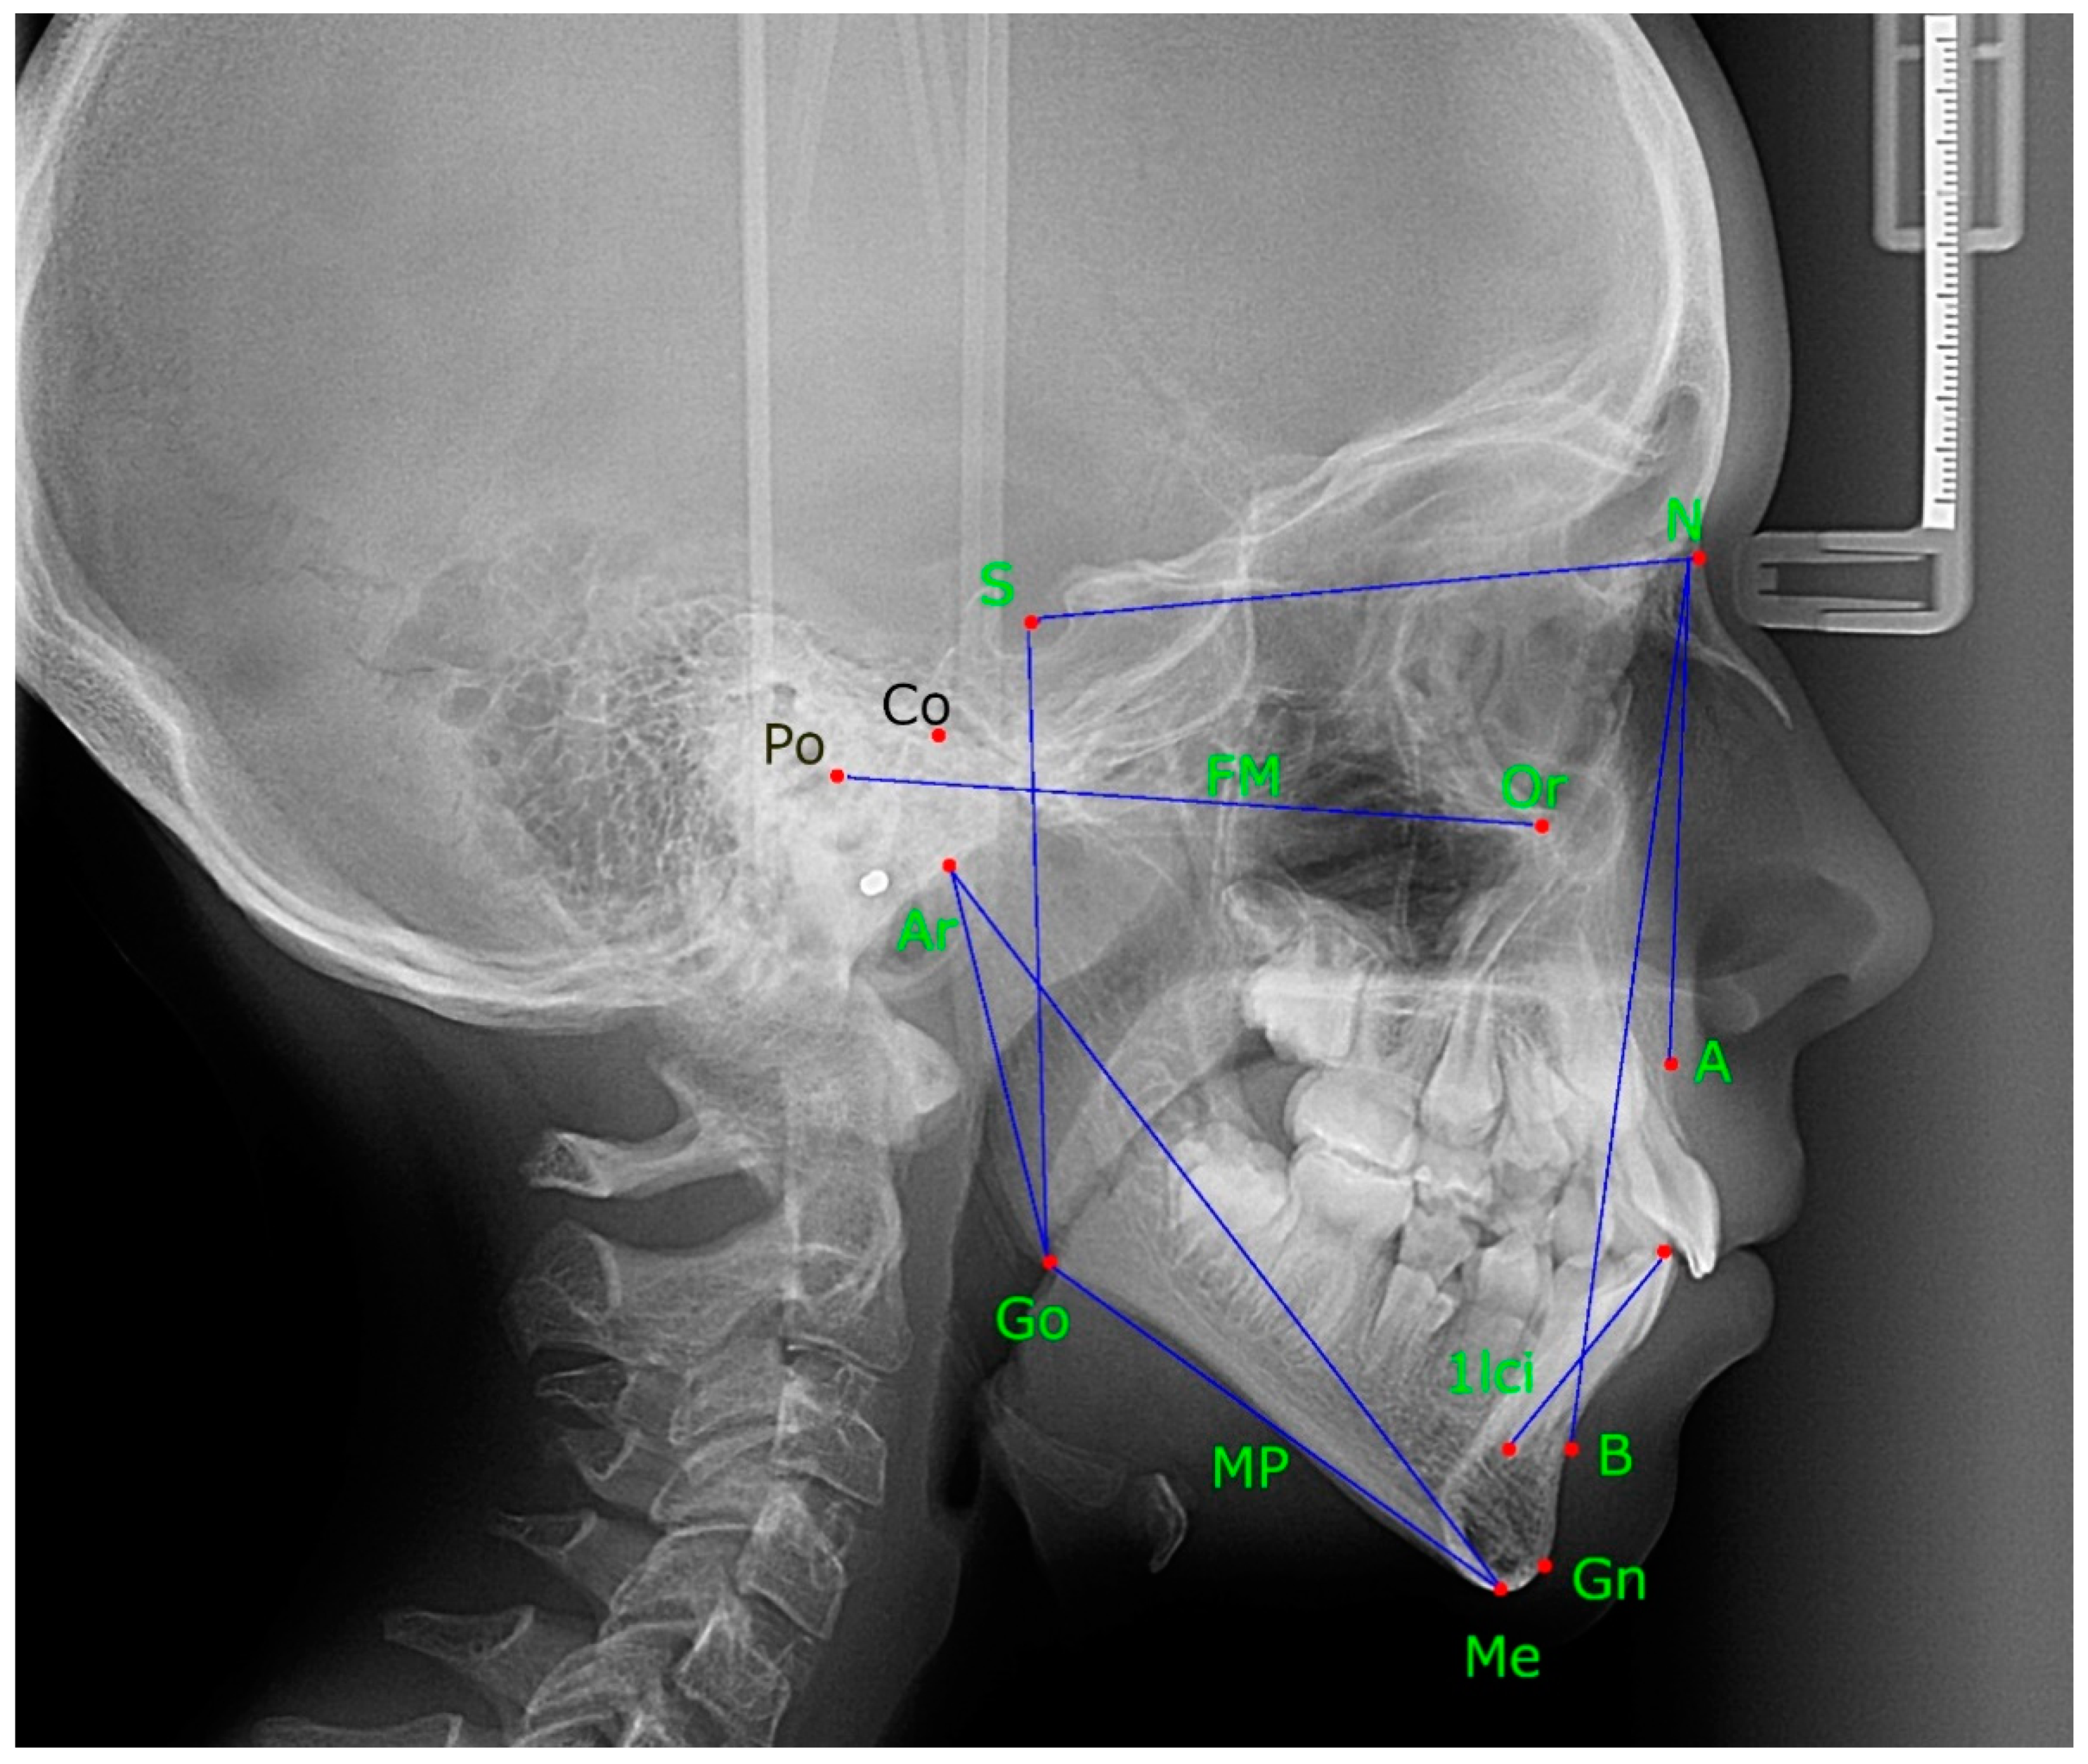

The following landmarks were measured: (1) basion–nasion (B-N), (2 ...

The following landmarks were measured: (4) nasion–anterior nasal ...

Cephalometric analysis. Measurements included (A) anterior midface ...

Lateral Cephalometric Skull Anatomy – Part I – Dr. G's Toothpix

A Beginners Guide to Lateral Cephalometric Radiographs